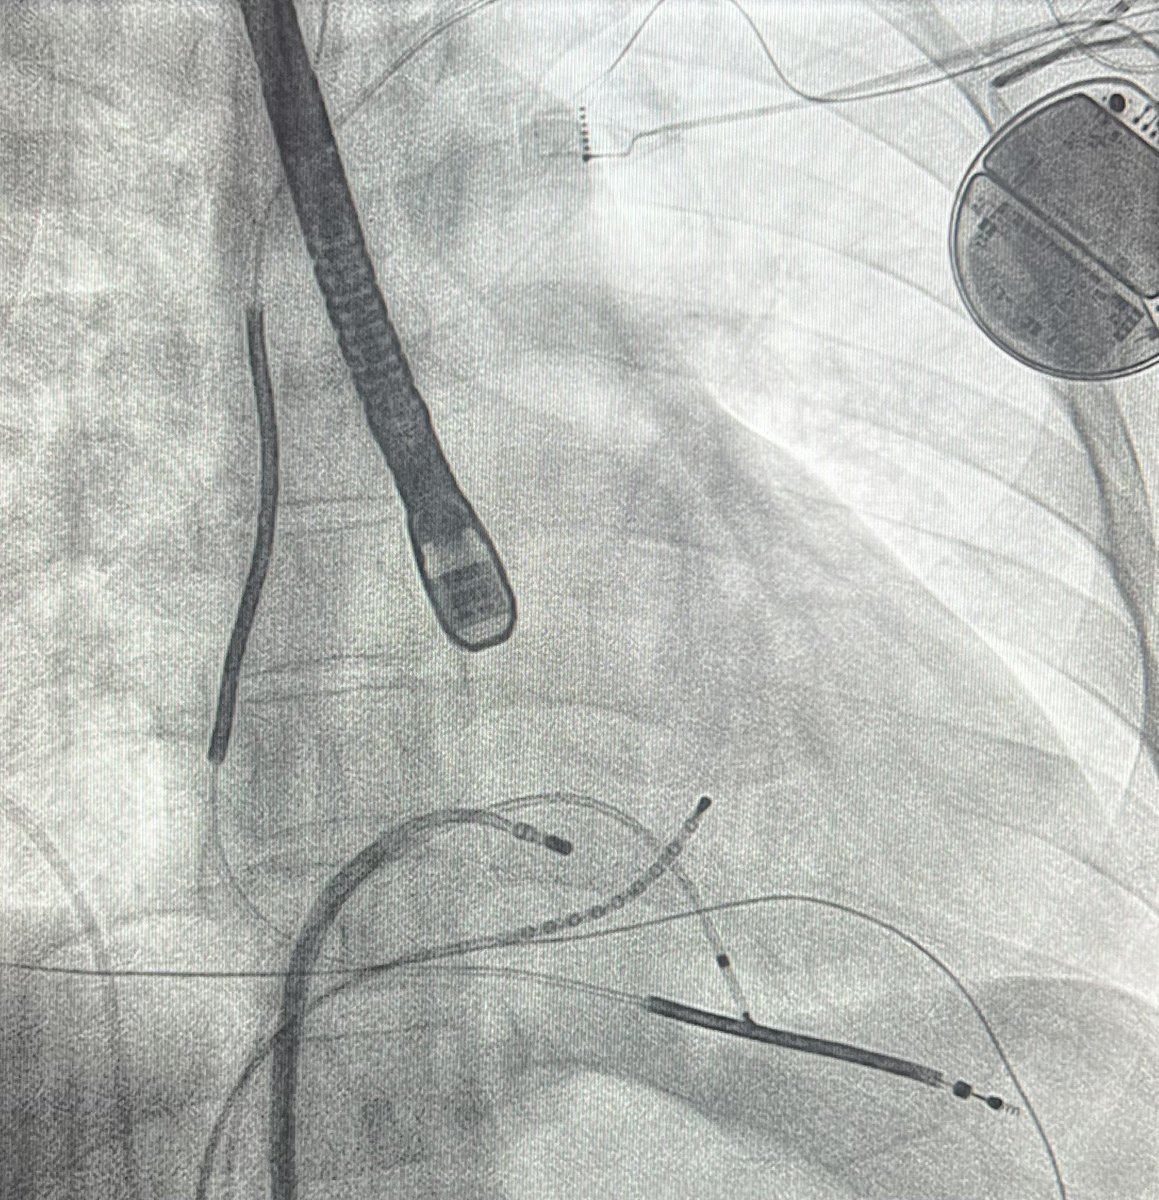

Impact of Left Atrial Posterior Wall Isolation using Pulsed-field Ablation in Patients Undergoing Repeat Catheter Ablation for Atrial Fibrillation #OpenAccess heartrhythmjournal.com/article/S1547-…